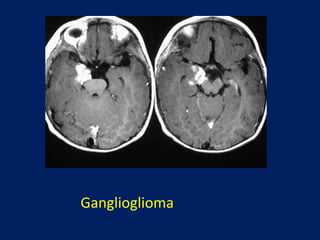

Ganglioglioma